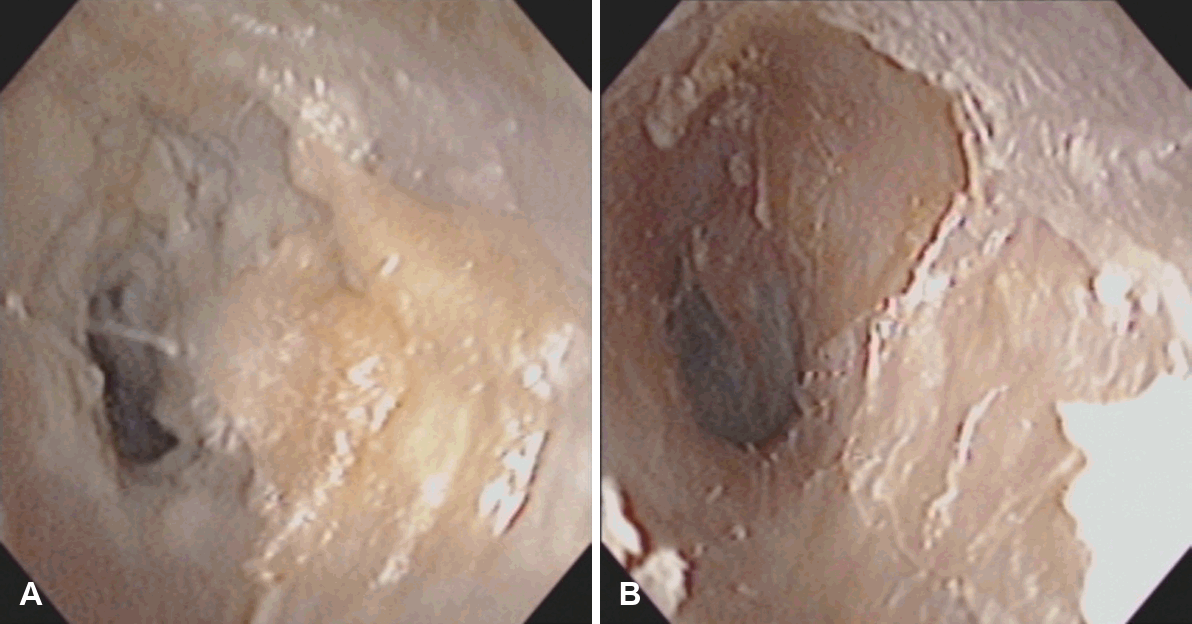

시술 전에는 이학적 검사와 영상 검사를 통해 외이도 직경에 비해 외이도 입구가 좁아져 있는지를 확인하여 환기를 저해할 만한 해부학적 요인을 파악해야 한다(Figs. 1 and 2A). 동시에 고막·중이 및 유양돌기 병변 유무를 확인하고, 진주 종이나 연조직 음영이 없는지 평가한다. 고막이 정상이며 이루 원인이 외이도 피부염 또는 협소한 입구로 인한 배출 장애로 의심되는 경우, 외래에서 세척과 국소 항생제 치료를 시행해 염증이 가라앉는지 관찰한 뒤 반복된 치료에도 호전이 없을 경우 시술을 계획한다.

Preoperative temporal bone CT demonstrating a narrowed external meatus (left ear). The CT scan shows a markedly narrowed external meatus (A, white arrow) compared to the diameter of the external auditory canal (B, yellow arrow).